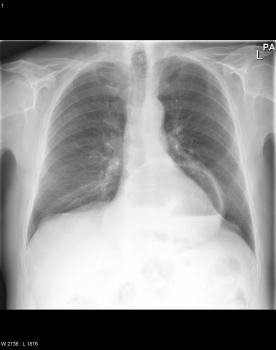

Image hydro -aerique

en niveau de estomac dans cas hernie hiatale par

roulement avec volvulus gastrique du partie hernie

du corp gastrique . Cliche pulmonaire de face |

Hernie hiatale par roulement

avecvolvulus gastrique de type mesenterico-axiale du

segment hernie du corps gastrique . Image

radiologique TDM en coupe sagitale . |